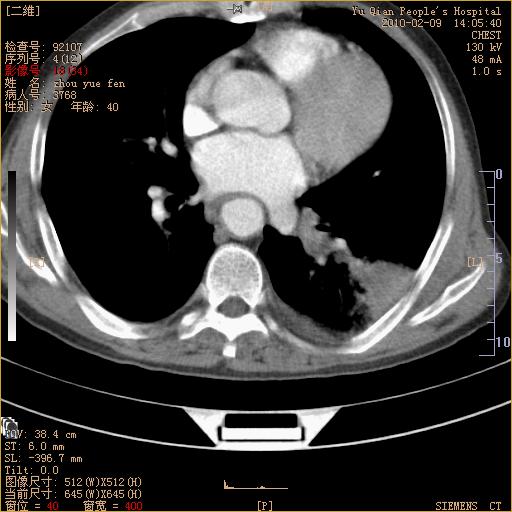

男性,73岁,咳嗽咳血数天,诊为肺ca伴左肺下叶后段阻塞性炎症、肺不张妥否?

右下肺有转移?

左下肺中央型肺癌伴结段形肺不张,左侧胸腔积液,纵隔内见部分增大淋巴结(反应性增生或转移)

左下基底干支气管明显变窄。

左肺下叶基底段支气管狭窄,左肺门增大,左肺下叶团片状病灶。中心型肺癌伴柱塞性炎症可能大,建议支气管镜检查。

左下肺中央型肺癌伴节段性肺不张,左侧胸腔积液,纵隔内见肿大淋巴结

左下基底段支气管变窄。建议进一步纤支镜检查。

1、左肺下叶后基地段肺癌伴阻塞性炎症,左下肺门淋巴结转移。2、左侧胸腔积液。